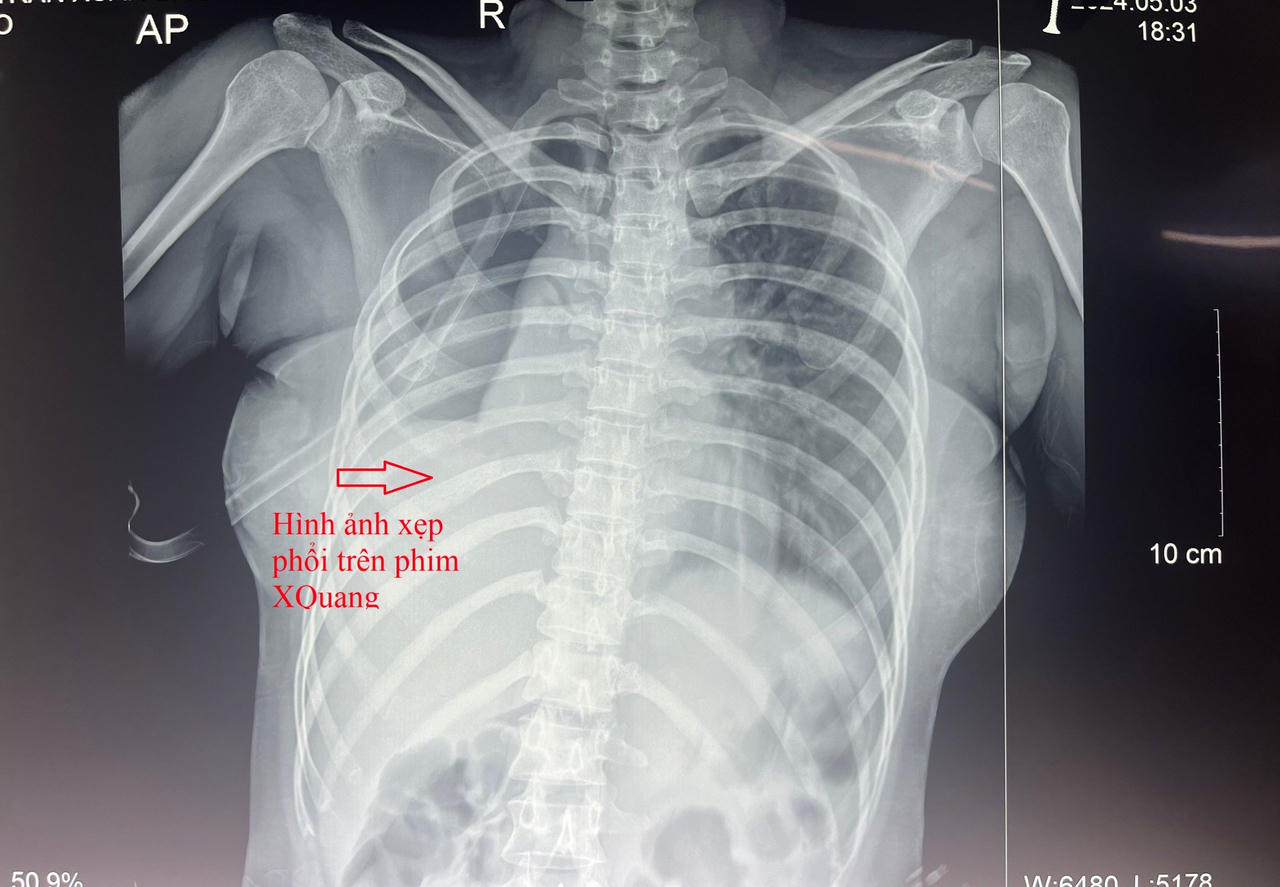

Hình ảnh xẹp phổi ,tràn khí màng phổi trên phim X-quang ngực |

Kết quả chẩn đoán xác định, bệnh nhân bị gãy xương sườn 1-2 bên phải và 1-5 bên trái, tổn thương phế nang phổi, tràn khí, tràn dịch màng phổi. Các bác sĩ tiến hành hội chẩn phẫu thuật. Ca phẫu thuật thành công sau 09 giờ căng thẳng. Hiện bệnh nhân đã tỉnh, phổi thông khí tốt, sức khỏe ổn định, đang được theo dõi và điều trị tại khoa Ngoại Lồng ngực – mạch máu.